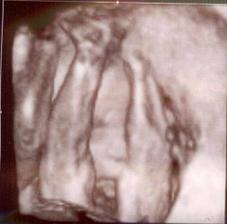

Toto je ten najkrajší zázrak na svete 🙂)) Dňa 10.6. 2009 potvrdená akcia srdiečka nášho bubáčika a rastieme ako z vody - máme 12,6 mm. Už teraz sa tešíme na prvú poradňu ktorá bude 1.7. na ktorej nám dajú vytúženú tehu knižočku a obrázok nášho zázraku 🙂)) Dňa 20.9. sme boli na 3D ultrazvuku, kde nám pán doktor povedal, že čakáme chlapčeka 🙂)) Tak sa z neho veľmi tešíme 🙂))